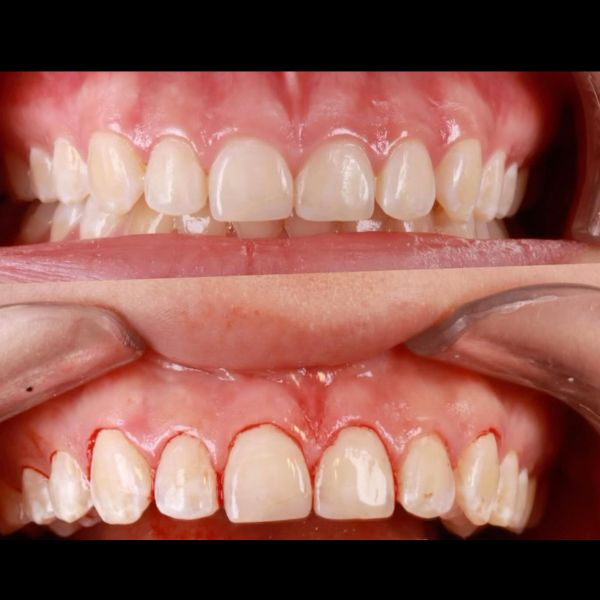

Before and After Gallery

Estoy completamente felizzzz , me realizaron implantes con coronas de Zirconio y láminas en cerámica en los dientes de adelante superiores y tuvo el mejor cuidado para complementar el color de mi dentadura de manera muy perfecta , la felicidad es toda , demasiado profesional y ética , estoy completamente feliz , Me hizo otros tratamientos donde implicaba mucho tiempo y la constancia y dedicación me sorprendió y lo logró en el menor tiempo posible , es sorprendente su empatía con el paciente, muchas gracias Doctora Eva